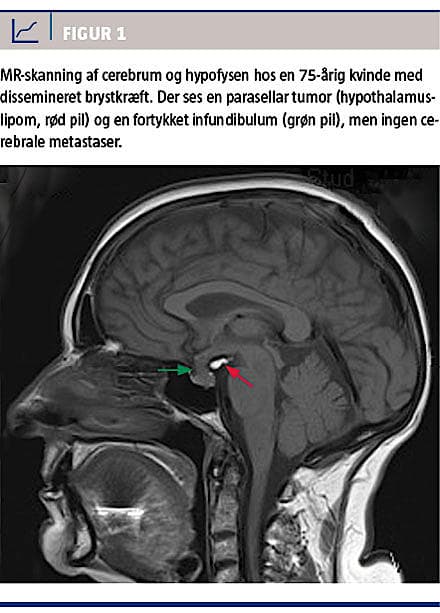

En MR-skanning af cerebrum viste fortykkelse af hypofysestilken og et 10 mm stort hypothalamuslipom bag denne, men ingen hjernemetastaser (Figur 1). Fortykkelsen af hypofysestilken blev af neuroradiologerne tolket som ikke værende af neoplastisk eller inflammatorisk oprindelse. Ved en kontrol-

MR-skanning efter tre måneder sås uændret hypothalamuslipom og regression af hypofysestilkens fortykkelse.